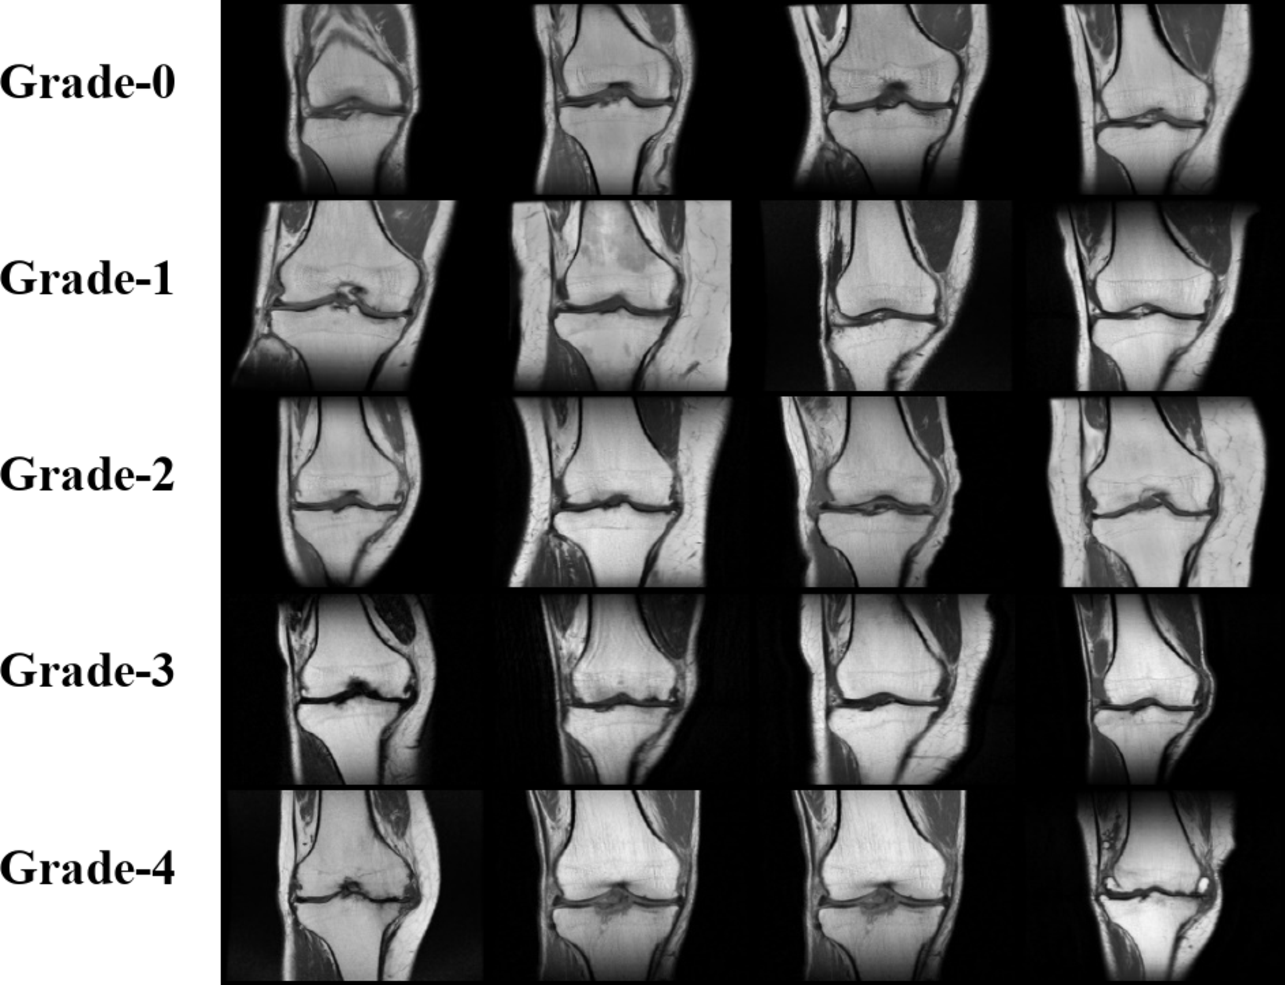

Fig. 4

Sample MR Images for Each Grade